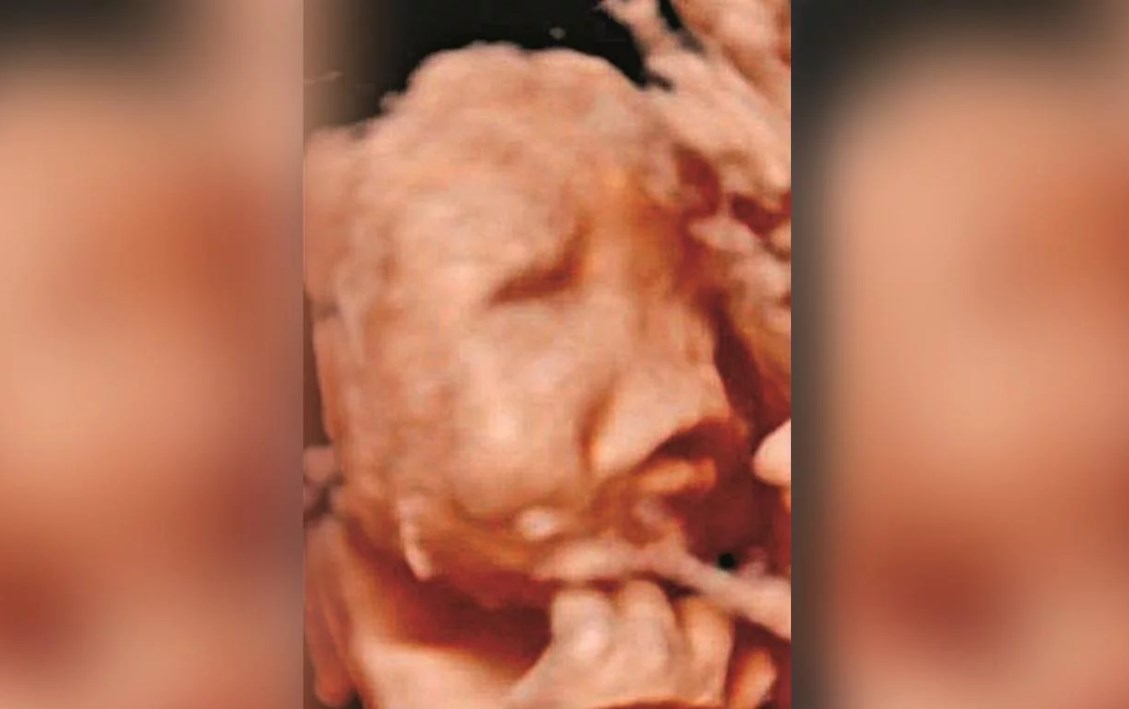

Durante la entrevista, los padres de Rodrigo mostraron uno de los ultrasonidos que les hizo el obstetra Artur Carvallo, que los atendió durante todo el embarazo y que jamás se dio cuenta de las malformaciones en el feto.

Pero como si eso fuera poco, el médico desestimó una cuarta en 5D que la madre se había hecho en otro centro médico y en la que sí les alertaron que algo no andaba bien.